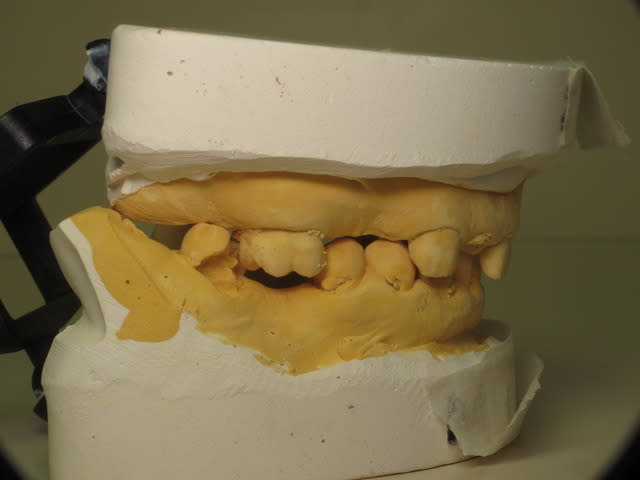

Le gros problème s'est l'occlusion. Côté gauche ça va et côté droit c'est la catastrophe. (voir les photos des modèles en occlusion)

Img 3756 soyc4i - Eugenol

Img 3757 voxbqp - Eugenol

Img 3758 xrmecb - Eugenol